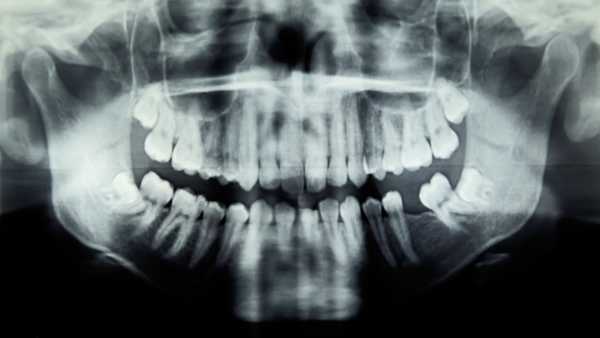

Близько 40% дорослих у США віком від 30 років мають певний рівень захворювання ясен, відоме як пародонтит, хронічне запальне захворювання, прогресування якого призводить до хиткості зубів, втрати зубів та постійного неприємного запаху з рота. У міру погіршення захворювання невеликі кишені навколо зубів, до яких неможливо дістатися зубною щіткою чи зубною ниткою, розширюються та заповнюються зубним нальотом і бактеріями.

У групі лікування пацієнти отримували інтенсивне лікування пародонтиту: ретельне очищення всієї ротової порожнини та глибоке очищення нижче лінії ясен для видалення зубного нальоту та зубного каменю. Контрольна група отримувала просте видалення зубного каменю та полірування, що більше схоже на звичайне чищення зубів, яке не включає глибоке очищення ясен.